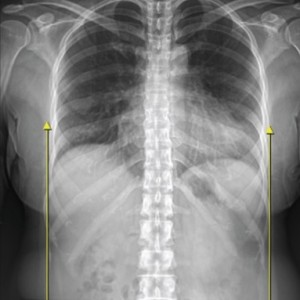

[ 척추 X 어깨 X 골반 X 족부 복합 치료 ]

01.

척추

척추측만증 또는 좌, 우 한쪽으로 기울어진 척추로 인해 체중이 한쪽 허리로 집중된다면 장기적으로 체중이 기울어진 쪽 허리에 뼈가 자라거나 퇴행성 변화가 빠르게 진행됩니다.

02.

어깨

목이 한쪽으로 기울거나 한쪽 어깨가 반대쪽에 비해 낮다면 상체의 무게가 한쪽 허리로 쏠리게 됩니다. 이때 낮은 쪽의 어깨는 광배근에 의해 허리로 연결되므로 어깨 높이 차이는 좌우 허리 근육의 불균형을 유발하여 허리 통증을 악화시킵니다.

03.

골반

허리는 골반위에 수직으로 서 있는 구조물이기 때문에 골반의 틀어짐은 필연적으로 허리를 틀어지게 만들어 허리에 많은 스트레스를 유발합니다. 만약 골반이 뒤로 기울어진 골반후방경사가 있다면 디스크탈출증을 더욱 악화시키며, 한쪽으로 회전되고 기울어진 골반은 체중이 집중되어 허리디스크와 협착증을 악화시키기 때문에 골반교정은 매우 중요합니다.